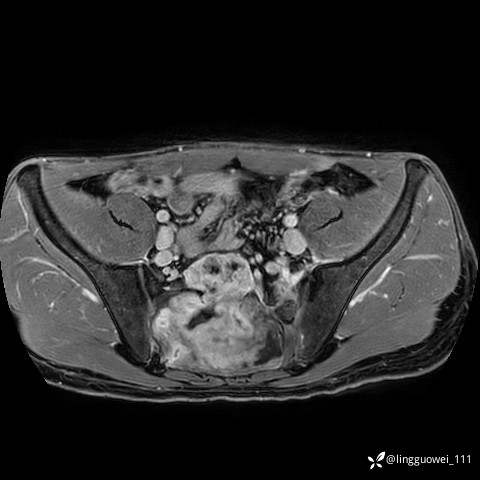

男,25岁,腰痛4年,加重左下肢痛5天,先上传X光片,第2天再上传CT。MR

MR:(忘记截图常规序列,不过应该不影响诊断)